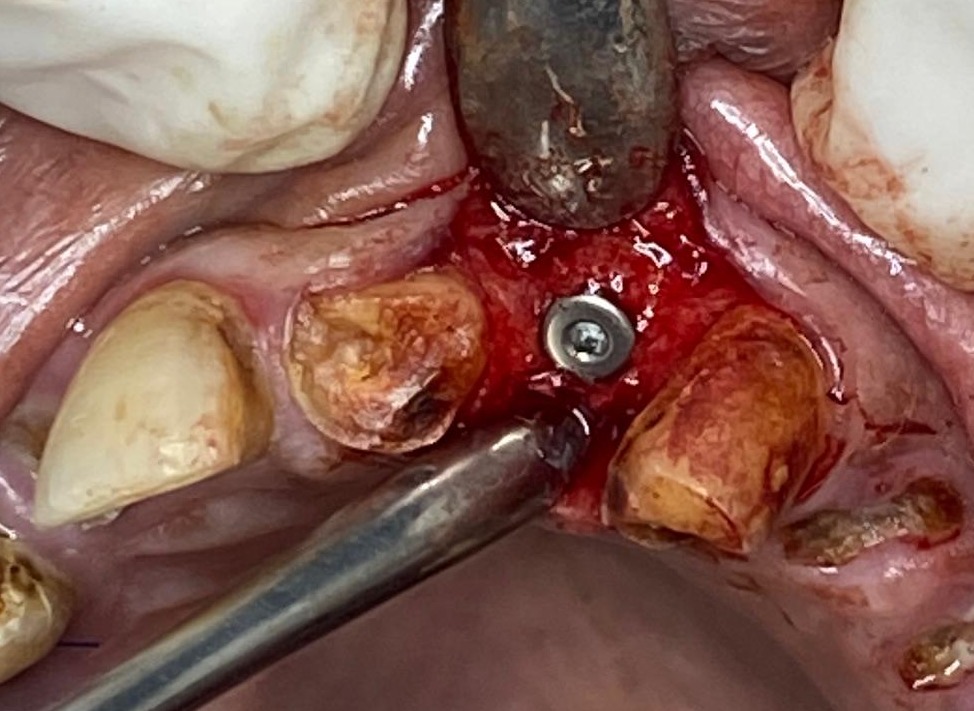

I used the machine today for extracting upper root piece it was a very good experience.

Usually with upper 4 rc treated root piece extraction can be stressful as the root piece keep breaking or crumbling and there is no grip for the root forcep. But with this extraction periotome tip it was really easy n no stress at all. I used elevator absolutely at the end as u can see it was hassle free n minimum bleeding .

Patient was very comfortable